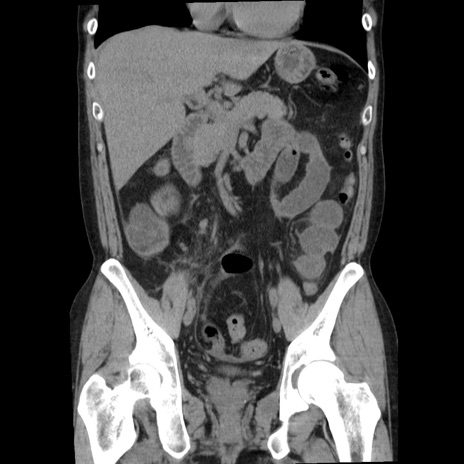

症例29(冠状断像)

【症例】40歳代男性

【現病歴】2日前から胃痛あり。徐々に周期的な激痛に変化した。本日になっても激痛があるため受診。

【身体所見】意識清明、BT 38-39℃台あり、腹部:膨満、やや硬、右下腹部に圧痛あり。

【データ】WBC 8500、CRP 23.26